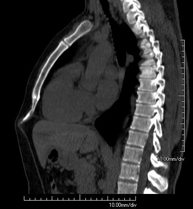

- TC Abdomen

Prueba diagnóstica que consiste en obtener imágenes del abdomen de alta definición anatómica (hígado, vesícula biliar, vía biliar, páncreas, bazo, estómago, intestinos, riñones, estructuras vasculares, vejiga, útero y ovarios, etc.) mediante el empleo de un equipo de TC (Tomografía Computarizada). Dichas imágenes se estudian posteriormente en una estación de trabajo que permite reconstrucciones bidimensionales en diferentes planos del espacio, y también reconstrucciones 3D (volumétricas). La mayoría de estudios requieren el empleo de contraste yodado para mejorar la definición de las imágenes.